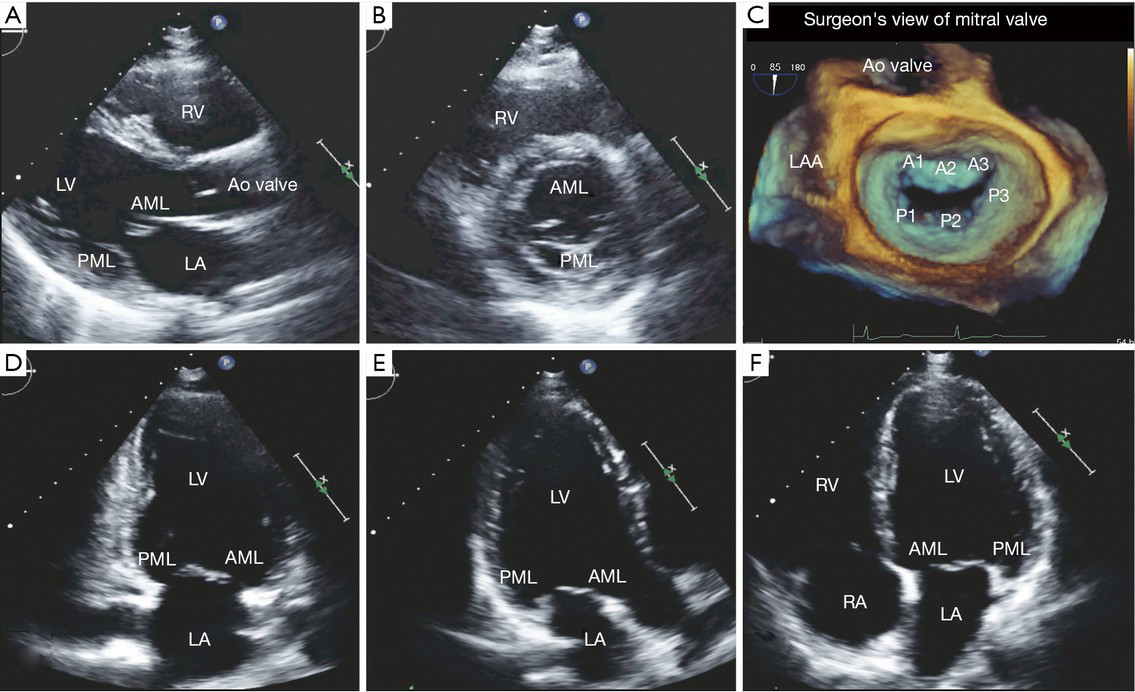

Describe the detailed anatomy of the mitral valve mv using two dimensional 2d transesophageal echocardiography tee based on the american society of echocardiographysociety of cardiovascular anesthesiology guidelines. Assessment of mitral valve dr. Accurate identification the anatomic lesions of the mitral valve echocardiography is pivotal in defining the functional anatomy of the mitral valve surgeon and echocardiographer speaking a common language mutual respect and honesty knowing when to send the.

The comprehensive tee examination of the mitral valve consists of a series of eight cross sectional views. Figure 20 1 mitral valve anatomy looking toward the left ventricle from posterior to anterior. Via chordae tendineae small tendons which ensure that the leaflets do not prolapse the valve leaflets are attached to two major papillary muscles anterolateral en posteromedial in the left ventricle.

Perturbations of the normal anatomic relations can result in mitral valve dysfunction table 3. The mitral valve consists of the mitral annulus anterior and posterior leaflets chordae tendineae and the papillary muscles. Assessment of mitral valve anatomy by real time 3 dimensional 3d transesophageal echocardiography tee has proven to be superior compared to 2 dimensional tee 121.

The mv comprises two leaflets annular attachment at the atrioventricular junction tendinous chords and the papillary muscles pms.